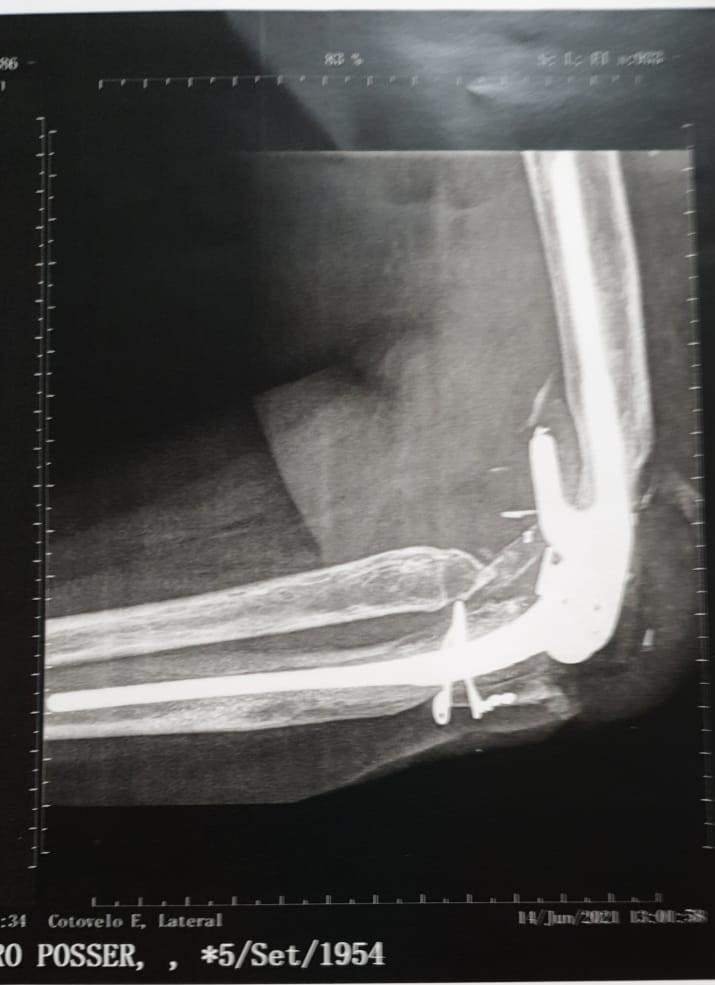

PRIMAVERA DO LESTE – Depois de sofrer um grave acidente de carro em 2002, Salete Posser, de 66 anos, quase perdeu o braço esquerdo. Na época, a empresária de Primavera do Leste foi submetida à cirurgia de artroplastia total no cotovelo, que é a reconstrução da articulação mediante a utilização de prótese. Quase 20 anos após a primeira cirurgia, a paciente precisou realizar novamente o procedimento para substituição da prótese, que ocorreu no último dia 02 de setembro, no Hospital Santa Rosa, em Cuiabá.![]()

Devido à complexidade deste tipo de cirurgia são poucos profissionais no país que realizam a artroplastia total no cotovelo. O primeiro procedimento de Mato Grosso foi o da empresária Salete, realizado em 2003, no Hospital Santa Rosa, em Cuiabá, por uma equipe que envolveu os médicos ortopedistas Marcelo Hide Matsumoto, referência nacional em cirurgias de membros superiores e cotovelo pela Escola Paulista de Medicina; e Maurício Allet, também especialista em cirurgia de mão e em reimplantes de membros, que atua desde 1999 em Mato Grosso com cirurgia de mão.

O segundo procedimento da empresária ocorreu mais recentemente, no início de setembro deste ano, e foi necessário devido ao desgaste natural dos componentes. Graças à prótese, Salete hoje tem uma vida normal, realizando todos os movimentos do braço e com sensibilidade em todos os dedos das mãos.

De acordo com Allet, é comum haver esses desgastes com o tempo. E para esta segunda cirurgia a equipe novamente contou com o médico Marcelo Matsumoto e com o chefe do grupo de Ombro e Cotovelo da residência do Hospital Santa Marcelina, de São Paulo, Anderson Uehara.

“Foram seis horas de cirurgia e além da substituição da prótese, onde colocamos um novo ‘cotovelo’, também tivemos que realizar a reconstrução de ligamentos, de músculos e colocar um enxerto ósseo, extraído do osso ilíaco (bacia). E novamente foi um sucesso, com a paciente se recuperando bem. Ela já mexeu o cotovelo no pós-operatório e está com a sensibilidade dos dedos da mão”, destaca Maurício.